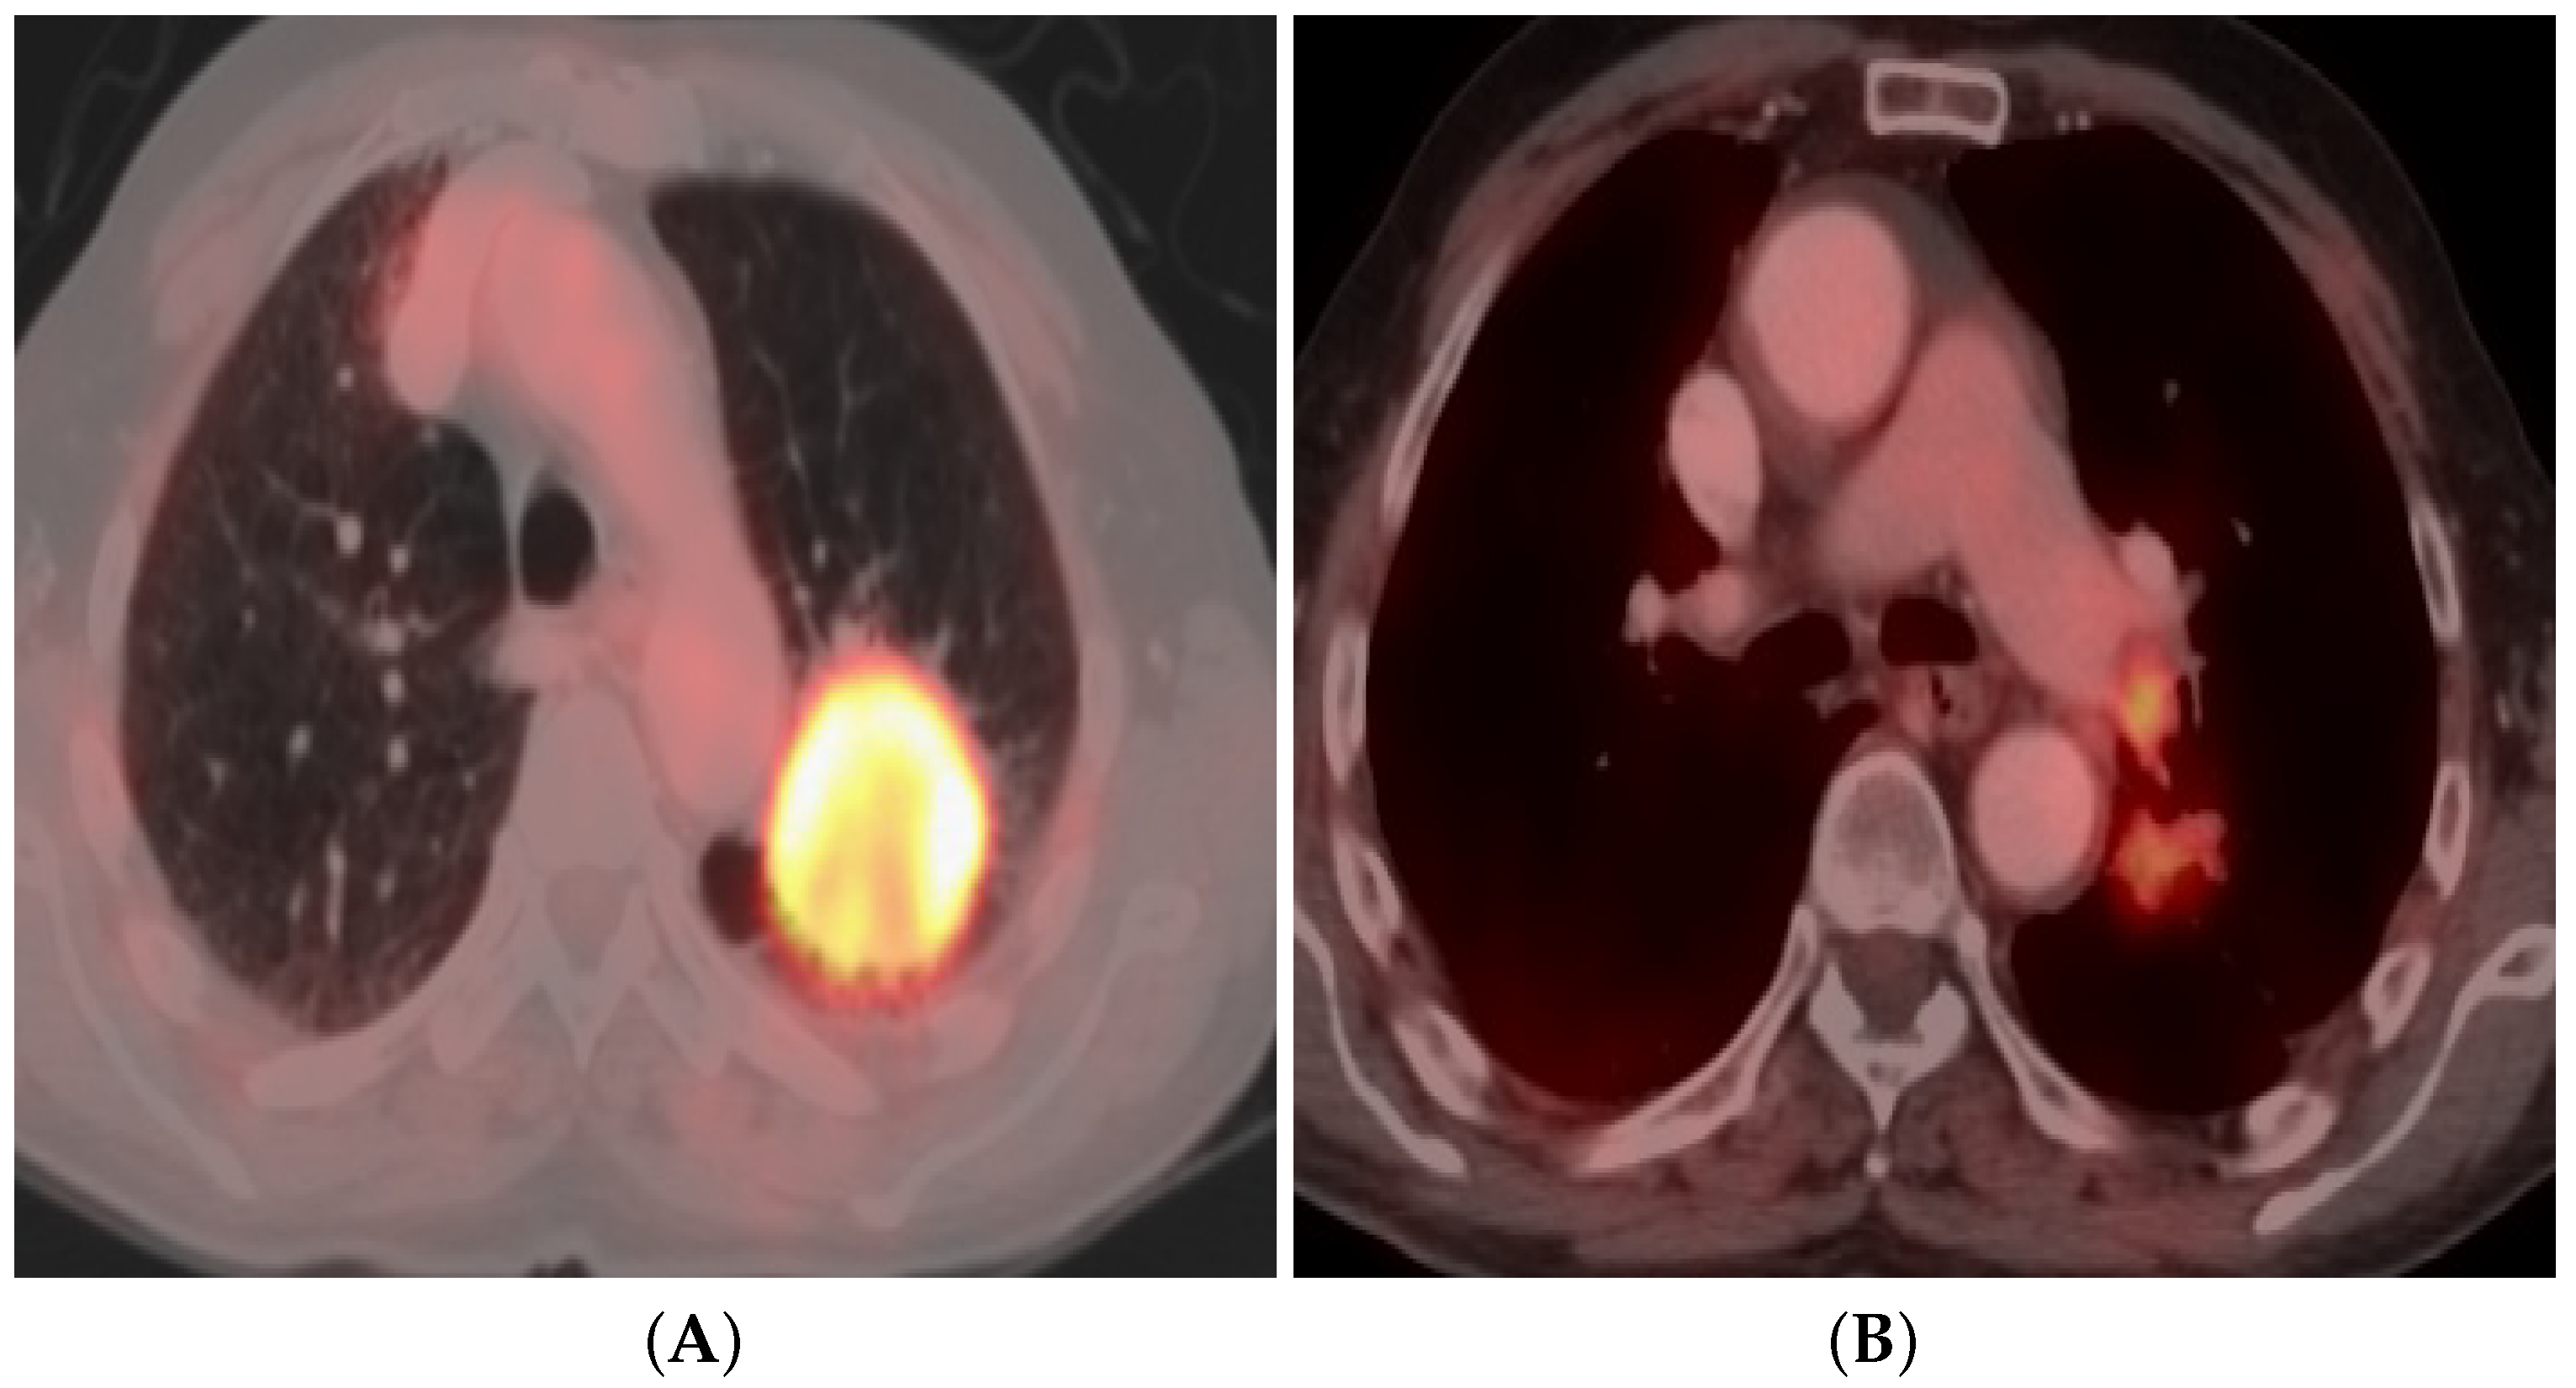

3.4. Positron Emission Tomography (PET/CT)

3.4.3. Qualitative Image Analysis

3.4.4. Quantitative Image Analysis

3.4.5. PET/CT Imaging Pitfalls